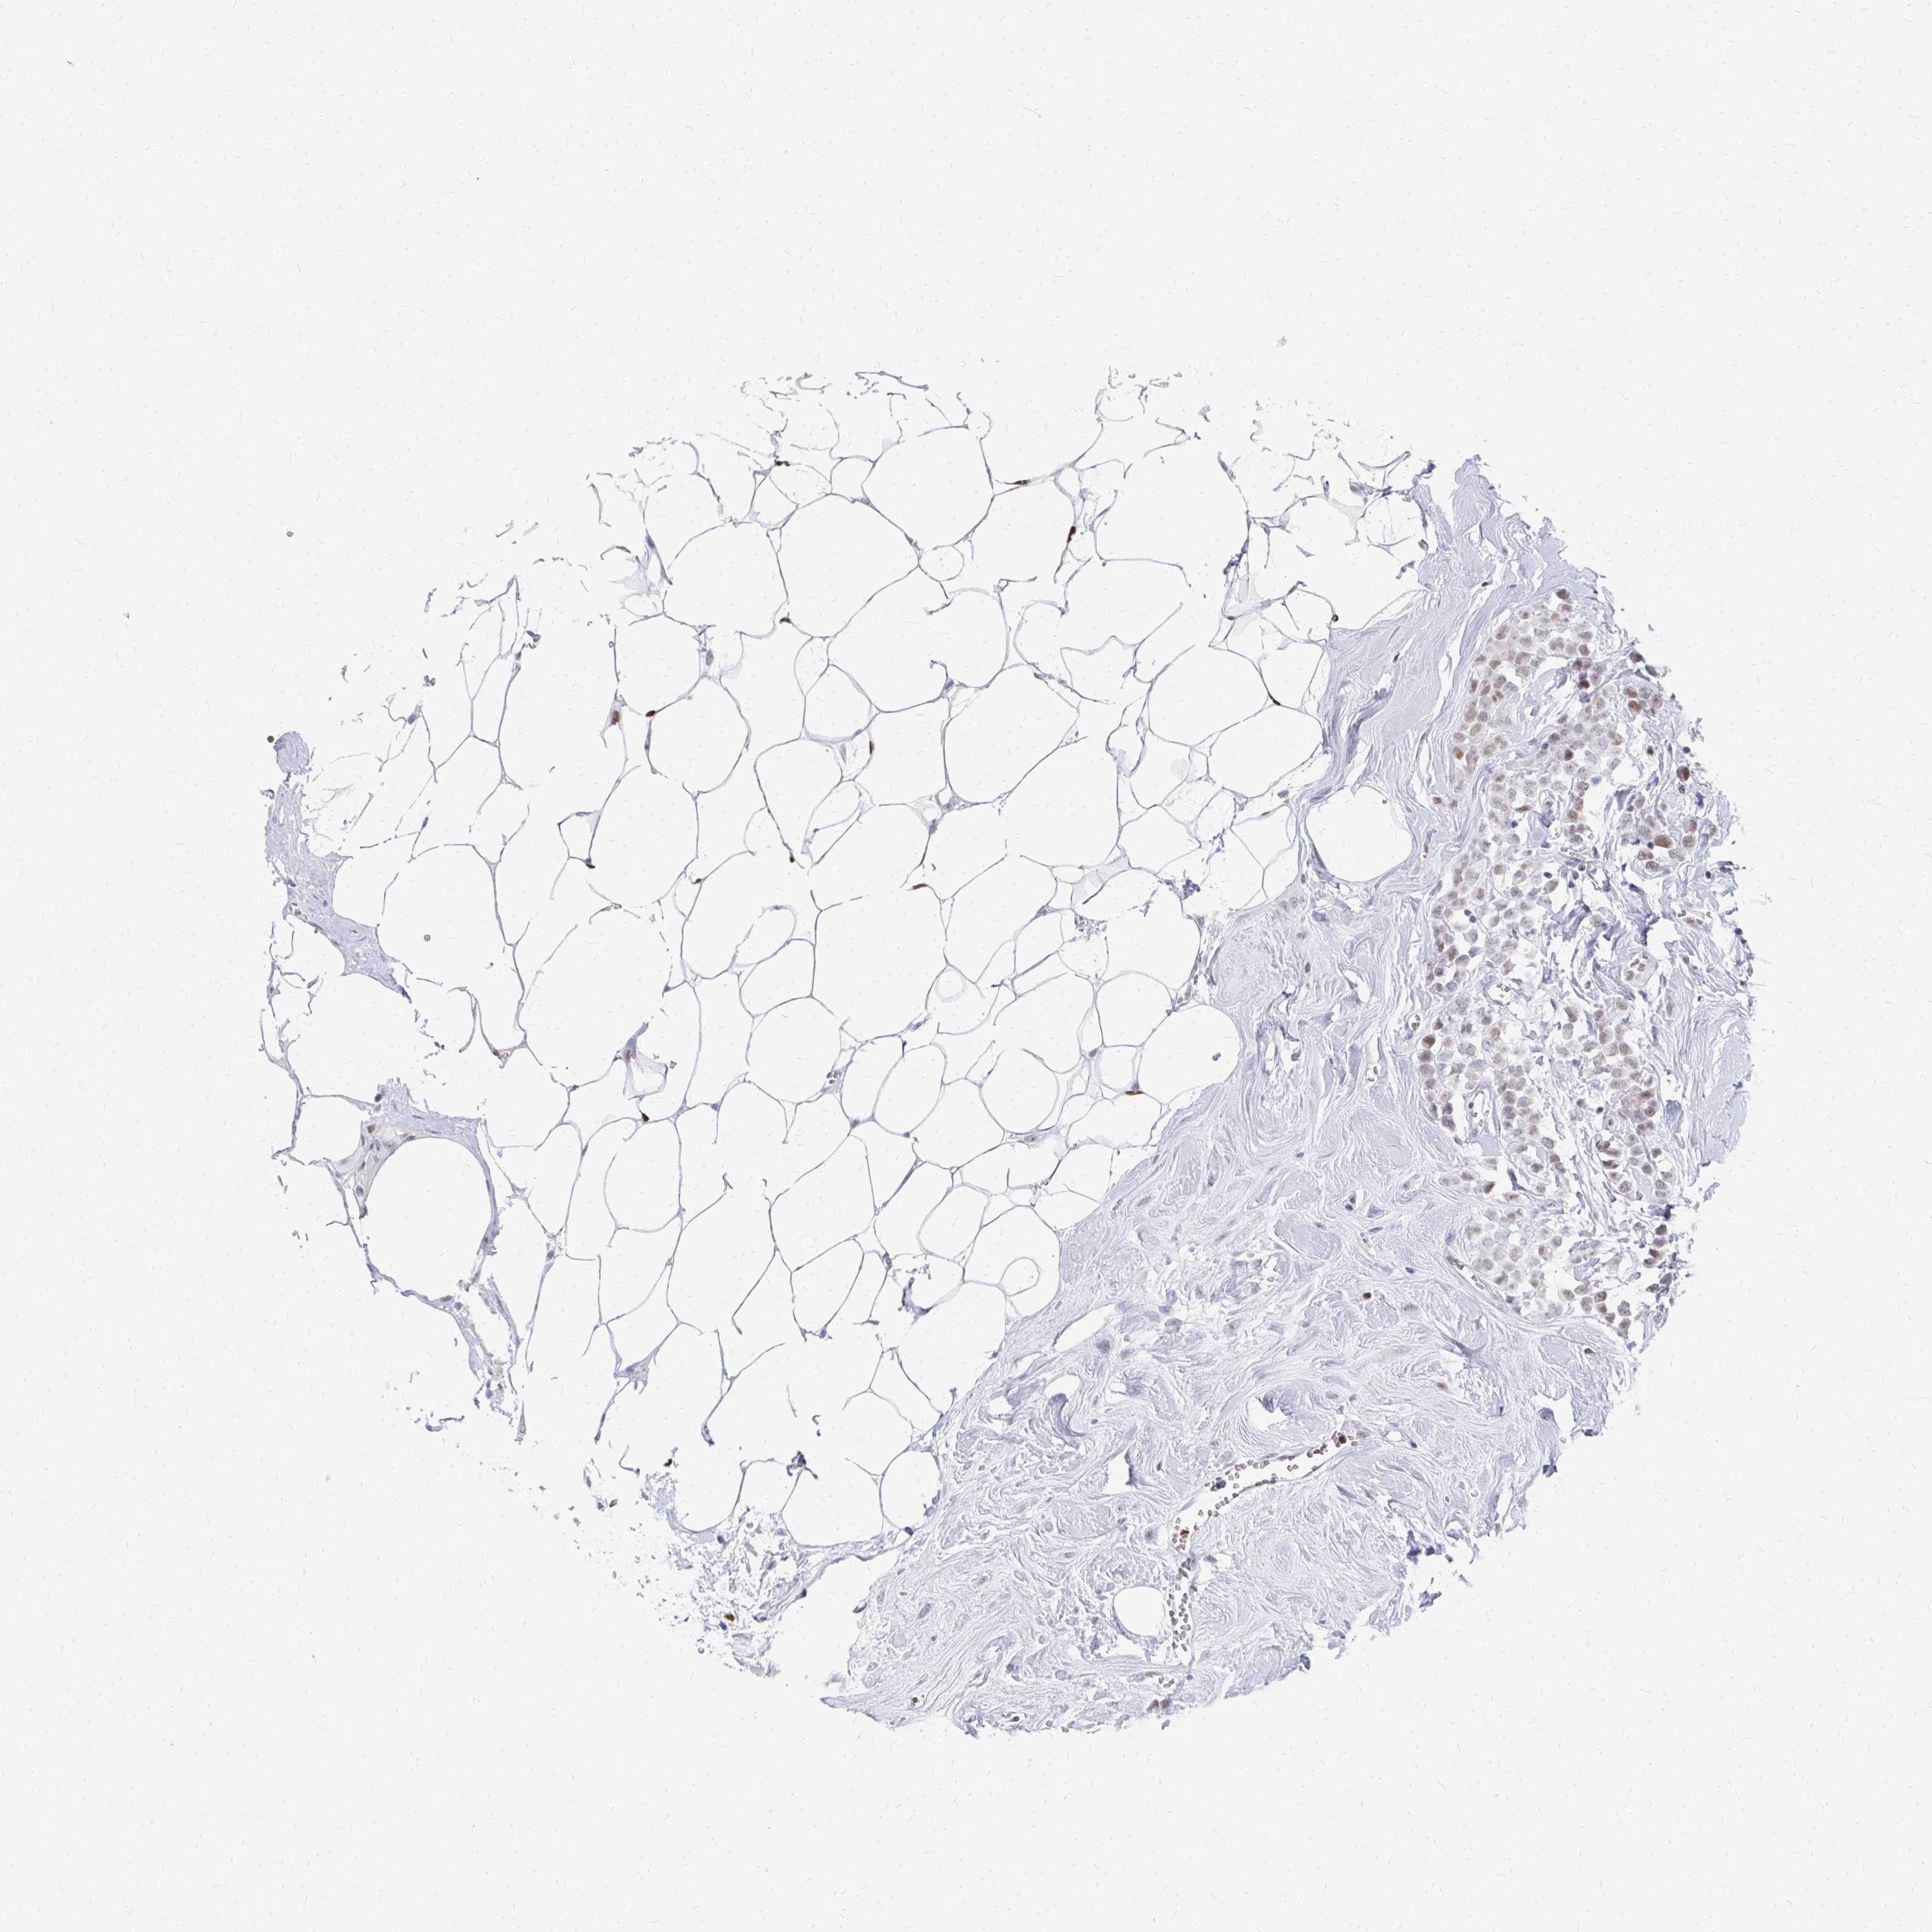

BRCA TCGA BRCA VALIDATION PROTEIN EXPRESSION